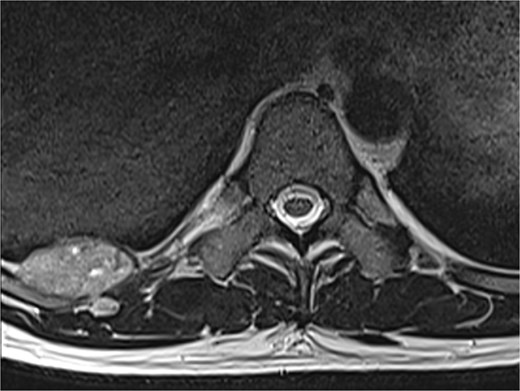

A 42-year-old male patient presented with intermittent pain under the right scapula for one year. The pain occurred both day and night, radiated to the right side of the abdomen, and improved with exercise. No skin lesions were observed. A thoracic spine magnetic resonance imaging scan showed a well-defined subpleural lesion on the right side along the ninth intercostal space posteriorly, which was hyperintense on T1-weighted imaging and isointense on T2-weighted imaging, with contrast enhancement features. The lesion size was 38 × 18 mm and extends into the back muscles with an additional nodule of 6 × 9 mm (Fig. 1). A contrast-enhanced computed tomography (CT) scan of the chest was performed to obtain a comprehensive chest view, revealing the same lesion without any other pathological findings (Fig. 2).

A magnetic resonance imaging scan shows a lesion on the right posterior side of the chest wall.